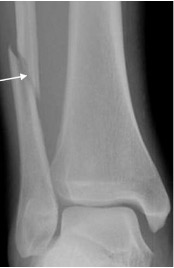

Stress fracture

- Occurs as a result of repetitive stresses or overload on bone

- Recognised sites include:

- tibia and fibula in long distance runners

- calcaneum and metatarsals secondary to walking (“March fracture”) and prolonged standing

- Seen as a linear band of sclerosis with periostitis